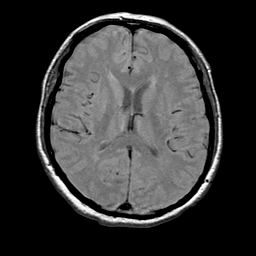

MR Study #1 -- Slice #13

[Home][Help][Clinical][Tour 1] Slice 13